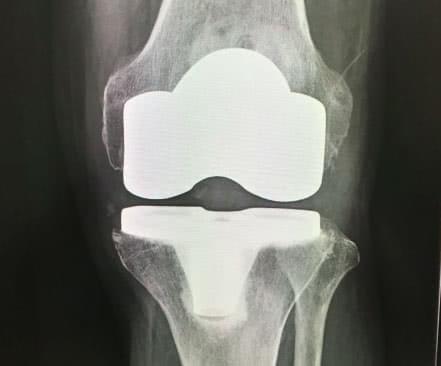

人工関節置換術

損傷した骨を削って形を整え、人工の関節をはめ込む手術です。部分的に人工関節と置き換える方法と、全体を置き換える方法の2種類がありますが、いずれも他の手術と異なるのは、問題のあるひざ関節の部分を取り除くことで、痛みをほぼ消失させられるという点です。手術自体に明確な年齢制限はありません。高齢であっても、リハビリを行える体力があり、手術について理解のできる方であれば、問題なく手術を受けられます。

手術時間は1〜2時間が目安。術後は早めにリハビリを開始します。退院は3〜4週間が一般的で、リハビリは退院後にも継続する必要があります。

一方、人工関節の付け替え(再置換)の可能性があることが、懸念点として挙げられます。インプラントにはチタン合金やポリエチレンなどの耐久性に優れた素材を使用しますが、摩耗や脱臼が起きてしまうと、一度取り外して付け替える手術が必要となるケースがあるのです。また、耐用年数を全うした場合も同様です。この手術を若年層に適応するかどうかの判断は、慎重に行う必要があります。

- 人工ひざ関節単顆置換術

- ひざ関節の内側か外側の損傷が激しい部分のみ、人工関節に置き換える方法です。

- 人工ひざ関節全置換術

- ひざ関節全体を人工の関節に置き換える手術です。